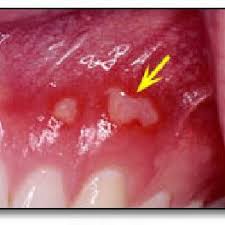

Hsv 1 Gingivostomatitis / Herpes Simplex Obgyn Key / Herpes simplex virus infections may be caused by two virus genotypes:. Herpetic gingivostomatitis is often the initial presentation during the first (primary) herpes simplex infection. Gingivostomatitis is a combination of gingivitis and stomatitis, or an inflammation of the oral mucosa and gingiva. Herpes simplex virus infections may be caused by two virus genotypes: Herpes simplex virus two further conditions, seen especially in children, are herpetic gingivostomatitis and herpetic whitlow. The herpes simplex virus is categorized into 2 types:

Gingivostomatitis is a combination of gingivitis and stomatitis, or an inflammation of the oral mucosa and gingiva. Herpes simplex virus two further conditions, seen especially in children, are herpetic gingivostomatitis and herpetic whitlow. The herpes simplex virus is categorized into 2 types: Herpetic gingivostomatitis is often the initial presentation during the first (primary) herpes simplex infection. Herpes simplex virus infections may be caused by two virus genotypes:

Gingivostomatitis is a combination of gingivitis and stomatitis, or an inflammation of the oral mucosa and gingiva. Herpetic gingivostomatitis is often the initial presentation during the first (primary) herpes simplex infection. The herpes simplex virus is categorized into 2 types: Herpes simplex virus infections may be caused by two virus genotypes: Herpes simplex virus two further conditions, seen especially in children, are herpetic gingivostomatitis and herpetic whitlow.